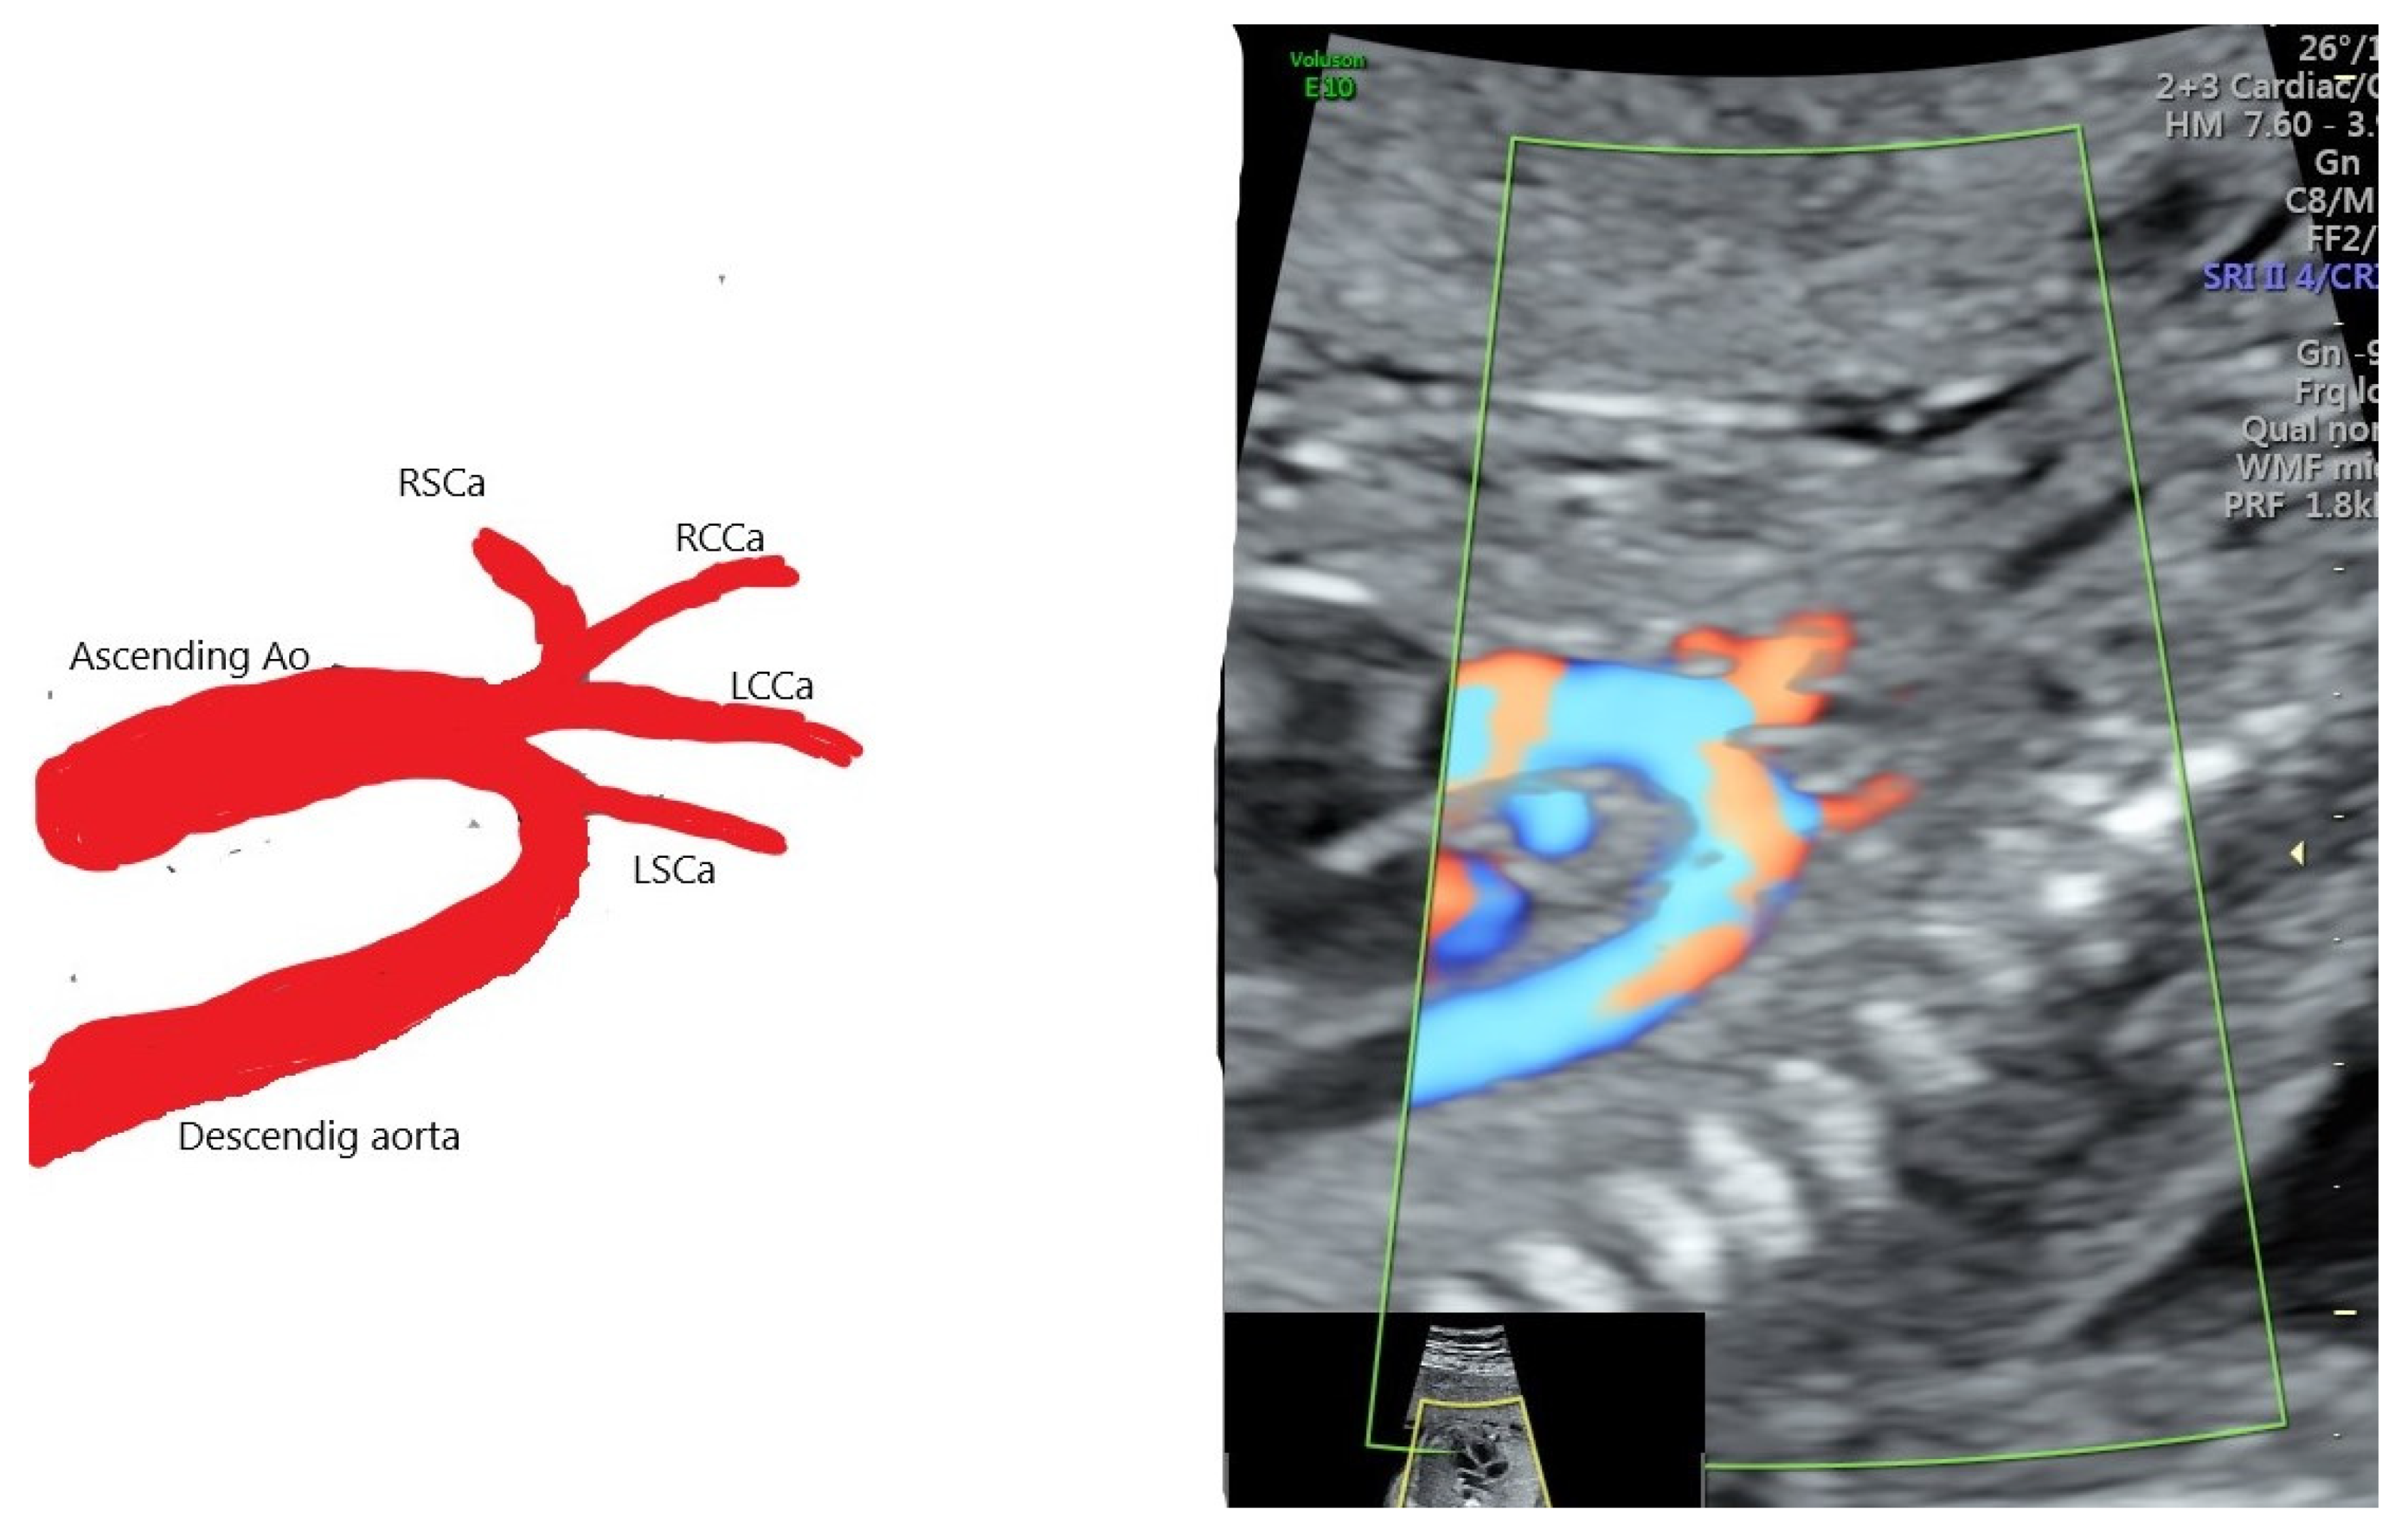

| 31 | 21 + 4 | 1 | type B | none | none | ND | Normal neonatal cardiac scan confirmed AAAV |